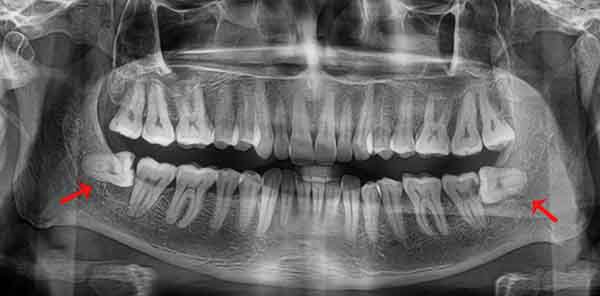

Sau khi thăm khám lâm sàng và chụp X-quang tại phòng khám, bác sĩ sẽ xác định mức độ mọc ngầm (ngang, xiên, chìm sâu) để đưa ra phác đồ:

Không thấy răng trồi lên: Đây là dấu hiệu cơ bản nhất. Nếu các răng khác đã mọc đầy đủ nhưng không thấy chiếc răng cuối cùng xuất hiện sau tuổi 18-20, cần đi chụp X-quang kiểm tra.